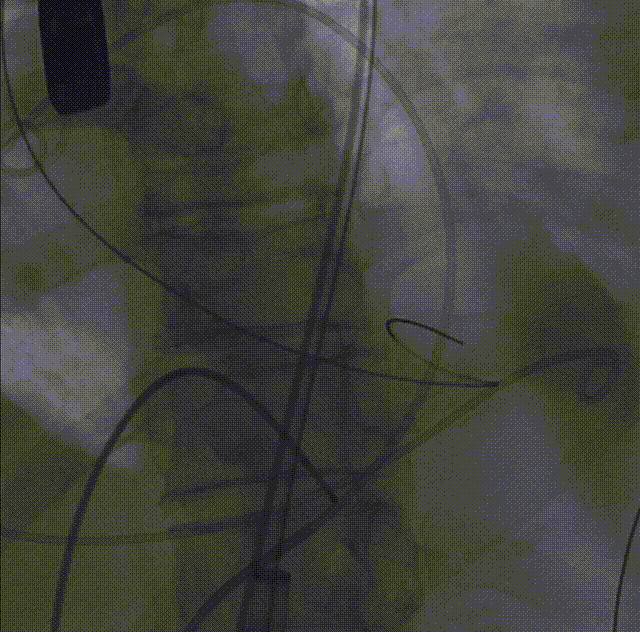

26VenusAplus+snare

瓣膜内22mm球囊后扩张,左冠无显影

LM烟囱支架植入4.0*30mm